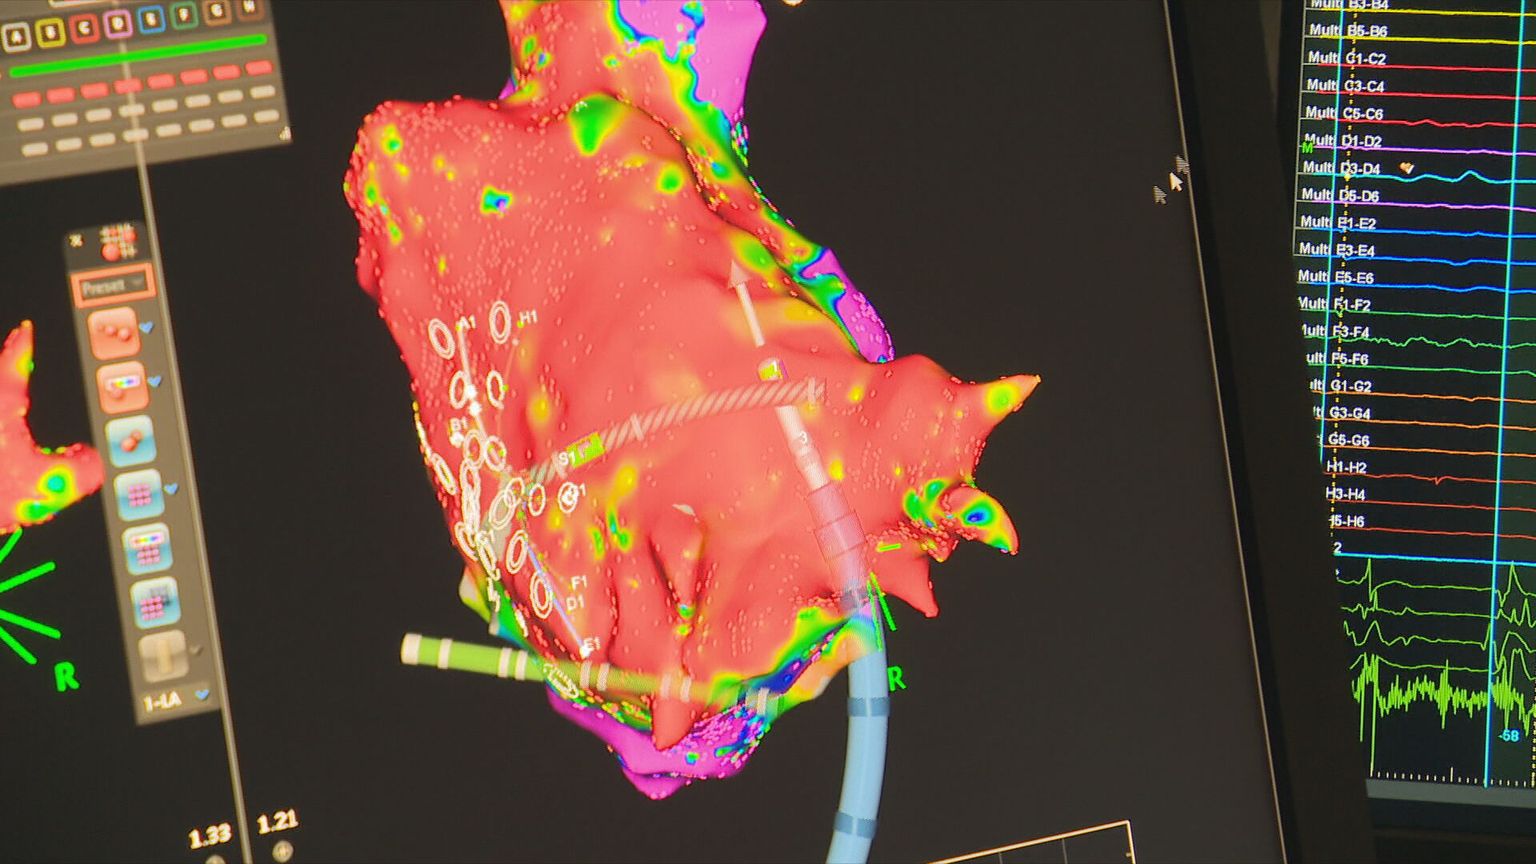

• Umjetna inteligencija u zdravstvu, ilustracija - 6 Foto: DNEVNIK.hr